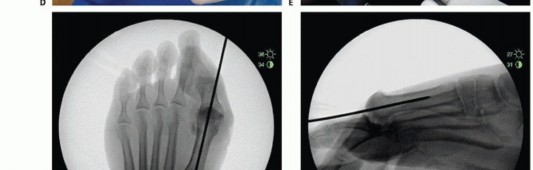

- TECH FIG 1 • Guide pin placement. A. Intraoperative picture of spherical guide placement just above the crista of the first metatarsal. B. AP view of pin placed in line with the long axis of the first MTP shaft. C. Lateral image of pin placed parallel to the long axis of the MTP shaft. The surgeon can drop his or her hand as necessary to match the inclination of metatarsal and midline within the shaft. (continued)

Place the centering guide pin on the metatarsal head in line with the long axis of the metatarsal shaft and verify its position on AP and lateral fluoroscopic views. Adjust the guide pin as necessary to obtain correct placement (TECH FIG 1A-E). Pay particular attention to the guide pin lateral view, for there is a tendency to underestimate the degree of inclination of the metatarsal shaft; parallel to the long axis of the shaft is the desired position. Adjust the pin before proceeding.

Use a cannulated step drill over the guide pin and drill to depth so that the proximal shoulder of the drill bit is flush with the articular surface (TECH FIG 1F-J).